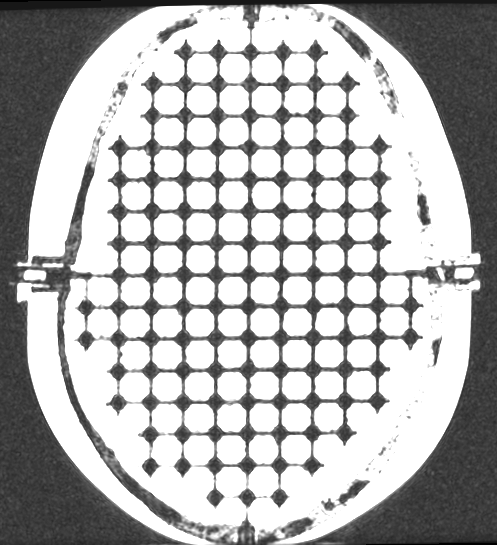

Finely Detailed Inter-Cranial 3D Design

The entire inter-cranial portion of the skull volume is filled with an orthogonal 3D grid of 2.5 mm diameter cross-like shaped rods spaced 10 mm (I-S), 10.5 mm (AP), and 11 mm (L-R). Extra material added in the grid intersections increases grid signal. Five extended axis-rods intersect at the reference origin of the grid. The end of each extended axis is fitted with CT/MR markers allowing for accurate positioning with lasers and co-registration of CT and MR image sets.

The phantom contains air voids on both sides that replicate ear canals. These voids are utilized to assess common distortions encountered in clinical settings.

The SRS MR Distortion Phantom can be imaged using X-ray, CT and MR. It images well with all MRI sequences tested to date, including T1 weighted, T2 weighted, 3D Time of Flight, MPRAGE and CISS.